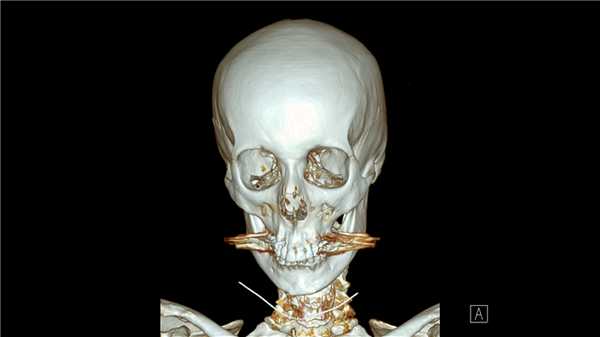

КТ при переломе назоэтмоидального комплекса

КТ лицевой части черепа и носа рекомендуют ЛОР-врачи, если пациента беспокоят фронтиты, гаймориты, этмоидиты, мастоидиты, а также после переломов носа. Компьютерная томография позволяет в высоком разрешении исследовать придаточные пазухи носа, барабанную полость, слуховые косточки. Перед проведением таких операций как септопластика (исправление искривленной носовой перегородки при затрудненном дыхании), а также ринопластика или риносептопластика, КТ - «золотой стандарт» оценки костно-хрящевых структур и анатомии носа.